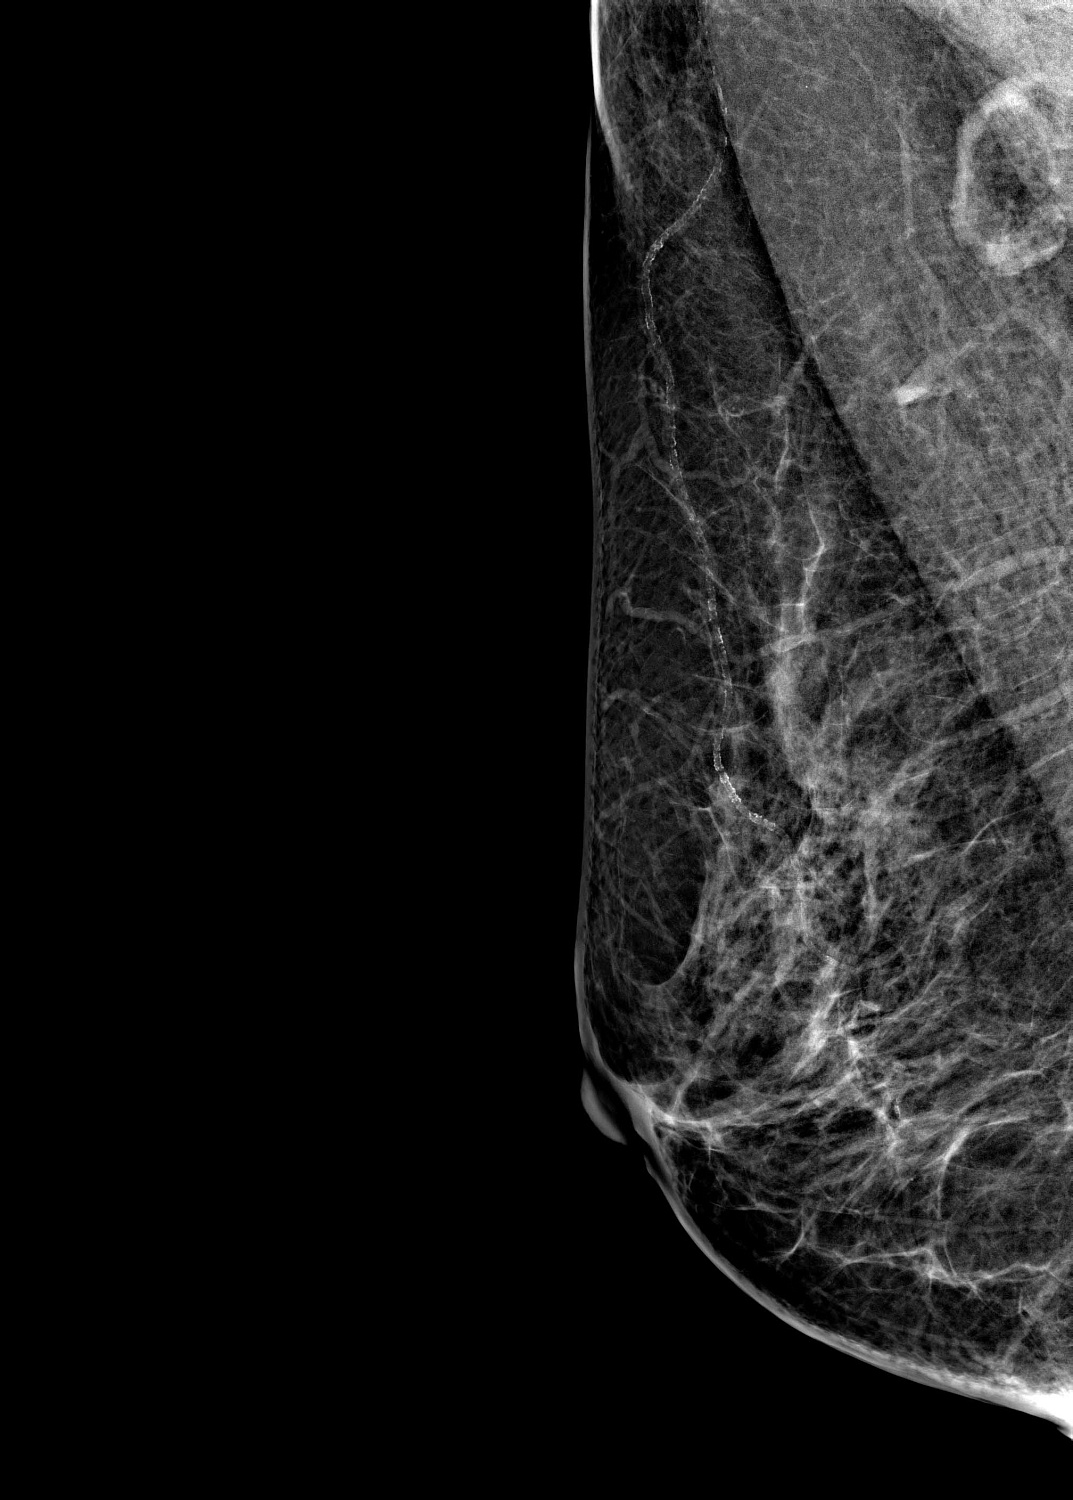

Маммограф выявляет опухоли молочной железы размером от 1-2 мм, которые не определяются при осмотре врача и самообследовании. На снимках хорошо различимы мельчайшие скопления солей кальция (от 87 мкм), тяжистые и другие перестройки тканей, характерные для рака груди 1-2 стадии. Высокую информативность, диагностическую ценность изображений обеспечивает цифровой детектор с самым чувствительным в мире сцинтиллятором. На снимках также определяются воспалительные процессы, кисты и даже небольшие повреждения.

Универсальный размер детектора делает обследование женщин с большим размером груди проще и безопаснее. Функция съемки молочных желез с имплантами позволяет обследовать эту категорию пациенток. На снимках хорошо различимы и ткани груди, и грудные эндопротезы.

Рентгеновский маммограф BRESTIGE EXPERT INDIRECT оснащен чувствительным сенсором непрямого преобразования на основе аморфного кремния. Цифровой детектор этого типа отличается надежностью и обеспечивает высокое качество изображения. Детальная «картинка» получается благодаря активной матрице, содержащей 2816 × 3584 пикселей, и хорошей квантовой эффективности (до 50%). На снимках ясно различимы даже небольшие изменения в структуре тканей и малоконтрастные образования.

Полноформатный детектор облегчает и ускоряет обследование женщин с большими молочными железами, а также делает его безопаснее. Пациенткам с грудью до пятого размера включительно для полноценного исследования достаточно 4 снимков: по 2 для каждой молочной железы. Аппараты, укомплектованные детектором меньшего размера, требуют 8 экспозиций.

Режим позволяет проводить маммографию у пациенток с грудными эндопротезами. На снимках хорошо видны ткани груди. Снимки отражают состояние импланта, в том числе его серьезные повреждения.